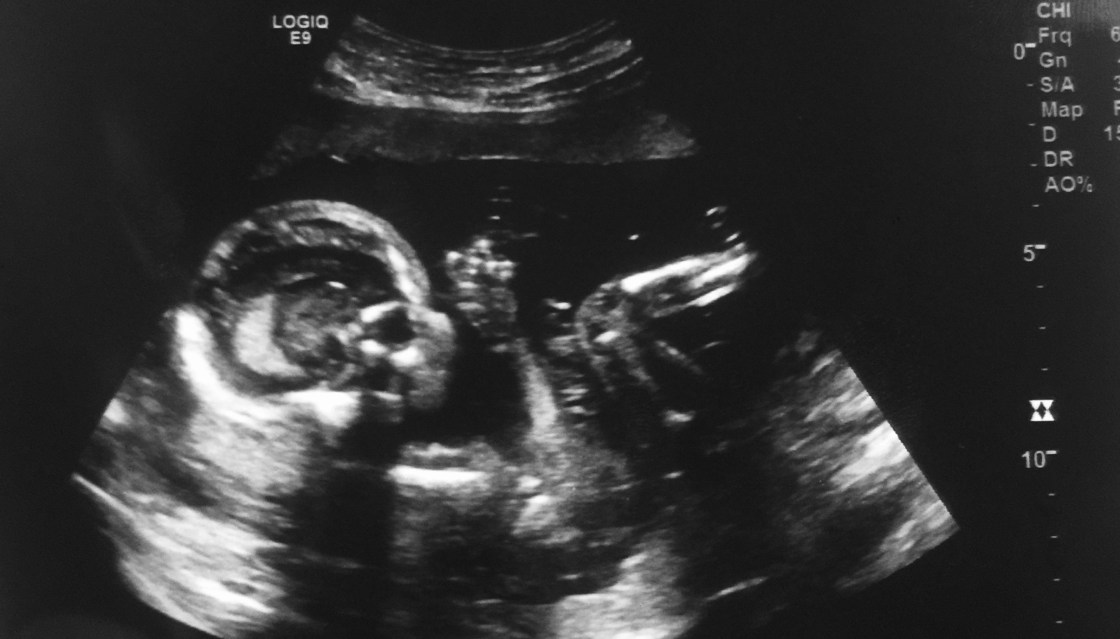

Little did I know what awaited us around the corner. Exactly one month later Kyler and I went in for our 20 week ultrasound scan to check the baby’s vitals. We excitedly told the ultrasound technician that we were having a boy and had chosen to name him Brody. As she scanned his kidneys, spine, brain, and length, she paused at his heart.

The technician spent another 10 minutes going over his little heart over and over again. Without a word, she exited the room, bringing with her another technician. This woman also went over his heart, eventually leaving the room to make a phone call. Within minutes, we were sent home without a word of explanation.